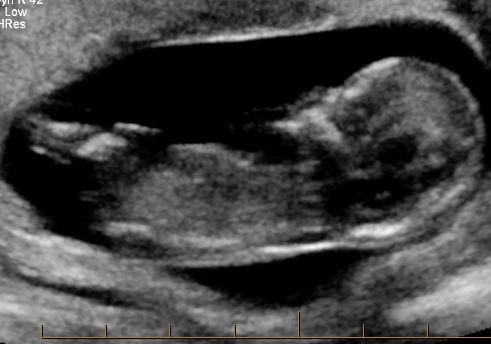

Guesses anyone? Was told boy at 12w2dAttachment 18706Attachment 18707Attachment 18708

Poss girl but not sure that's the nub?!?

Too early for a potty shot, and I don't see a nub. But I don't see anything obvious in the potty shot, so slight girl lean.

No nub, can't go by potty shot.

Anyone?